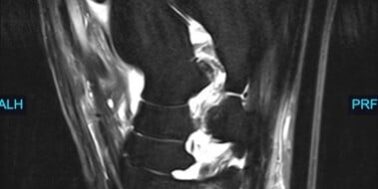

At Animal Imaging, Hugo was placed under general anesthesia and multiplanar MR images were acquired. The gelding was found to have moderate to marked, ill-defined fiber disruption of the origin of the proximal suspensory ligament with marked subchondral and endosteal sclerosis of proximal plantar third metatarsal. The proximal and body of the suspensory ligament was generally enlarged and rounded. The gelding also had marked subchondral sclerosis of dorsal central and third tarsal bones. Numerous, small cortical and subchondral cystic lesions of the dorsal distal intertarsal and tarsometatarsal joints.

Hugo was diagnosed with subchondral bone injury of third metatarsal bone with concurrent marked enthesitis and desmopathy of the origin of the proximal suspensory ligament. The gelding also had moderate to marked chronic desmopathy of the proximal suspensory ligament and body and Moderate to marked distal intertarsal and tarsometatarsal osteoarthropathy.